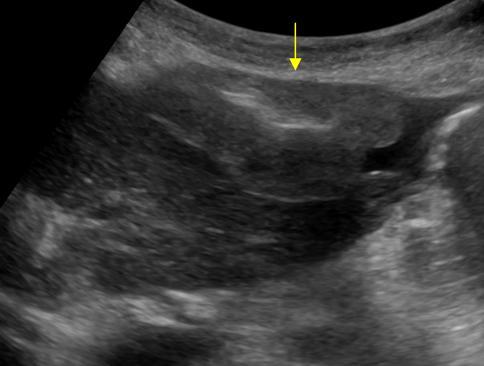

Di căn phúc mạc - Ảnh 4

Di căn phúc mạc

» Thông tin: Nữ giới – 55 tuổi.

» Lâm sàng: Đau bụng / K buồng trứng.